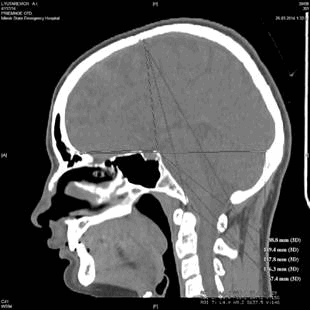

Двухмерные снимки в горизонтальной и сагиттальной плоскостях позволяют произвести необходимые измерения параметров черепа с точностью до 0,1 мм. Для удобства измерений рекомендуется отметить фиксированными координатами те или иные краниометрические точки на внутреннем основании и своде черепа, необходимые для измерения соответствующих параметров черепа. Для того, чтобы произвести измерение, необходимо воспользоваться инструментом «Электронная линейка». Измерение производится путем перетягивания курсора между краниометрическими точками. Результат отображается на мониторе справа в мм (рис. 2).

Рис. 2. Измерение краниометрических параметров в сагиттальной плоскости (слева) и в горизонтальной плоскости (справа)